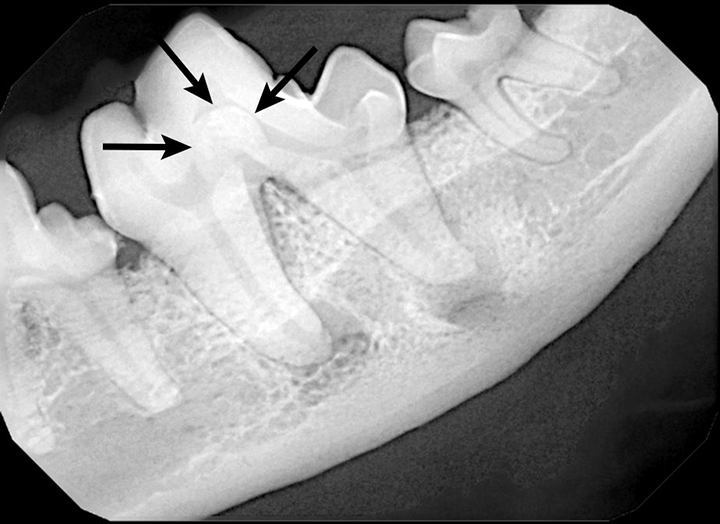

Dental Radiography Taking the Xrays OSU CVM Veterinary Clinical Dental Radiographs Practice the american dental association (ada) has various policies and recommendations to help dentists ensure that patients’. the european academy of paediatric dentistry (eapd) proposes this best clinical practice guidance to help. quiz yourself with questions and answers for dental radiology practice test, so you can be ready for test day. This article provides the fundamentals of. . Dental Radiographs Practice.